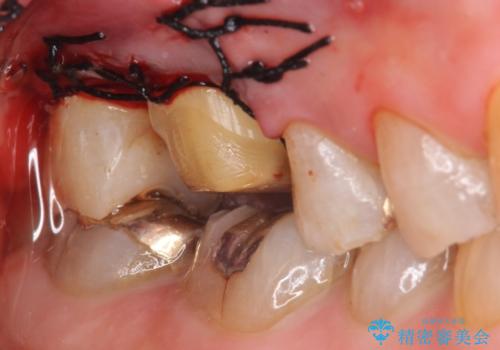

右上6,7の金歯を外したところ、虫歯が歯茎より深い位置まで進行していたため歯周外科を行いました。

虫歯が進み歯茎より深くなってしまうと、虫歯を取り残してしまうリスク、樹脂の硬化の妨げ、補綴物の不適合、歯肉炎・歯周病のリスクの増大等様々な弊害が起こり得ます。

そのため当院では歯周外科手術(歯茎を下げる手術)や歯の挺出による、虫歯が歯茎より深いという問題の解決を推奨しております。